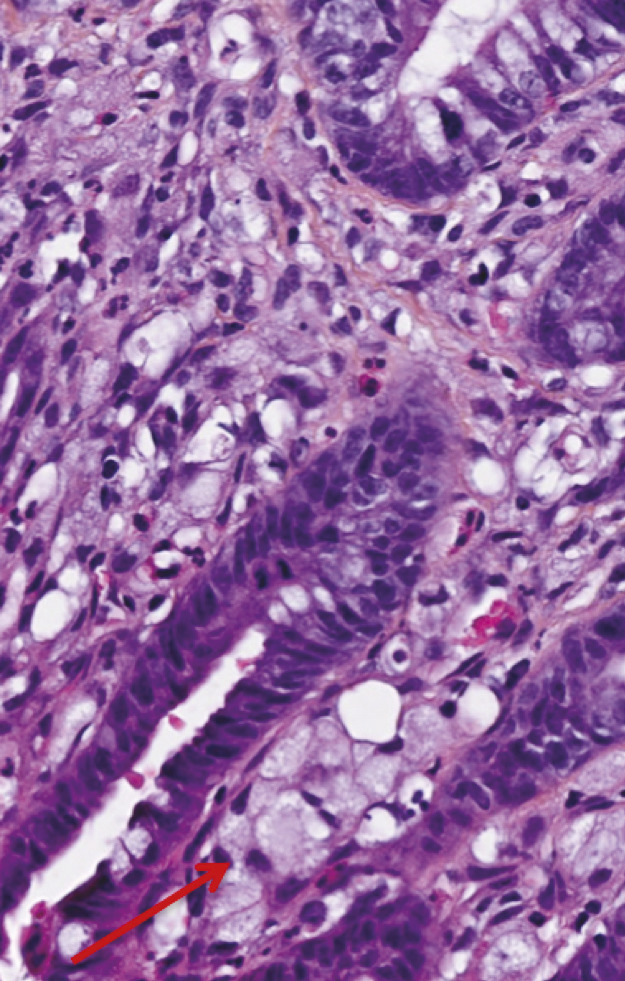

La classification des cancers gastriques est complexe puisque plusieurs types histologiques peuvent coexister au sein d’une même tumeur. Par ailleurs, différentes classifications histologiques sont utilisées en pratique courante et dans les études, avec des valeurs pronostiques variables. L’adéno- carcinome gastrique à cellules indépendantes (ADCI) est défini comme étant un adénocarcinome gastrique comportant un contingent majoritaire (plus de 50 % de la tumeur) de cellules isolées ou de petits groupes de cellules disséminées dans un stroma particulièrement fibreux et contenant de la mucine en intracytoplasmique (fig. 1) [v. encadré2, 3]. Il a une épidémiologie et un pronostic propre. Il est, en effet, plus fréquemment observé chez les sujets jeunes et est diagnostiqué à un stade plus avancé que les autres types histologiques. Il est également associé à un pronostic plus sombre, que ce soit sur la survie globale ou la survie sans récidive.4

L’examen anatomopathologique de la pièce opératoire montre l’existence d’un adénocarcinome peu différencié de l’antre gastrique, de 42 x 23 mm, avec un contingent majoritaire de cellules isolées en bague à chaton (60 %) dans un stroma fibreux. La lésion est classée pT3N1Mx. La réponse à la chimiothérapie préopératoire est moyenne, estimée selon la classification de Mandard à TRG3. Les marges de résection sont saines d’envahissement tumoral (R0).